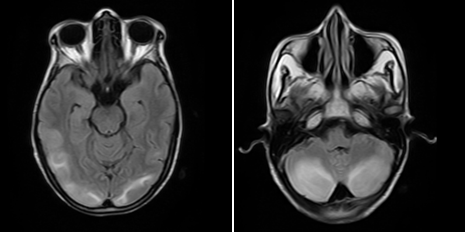

On examination, she was confused with the Glassgow Coma Scale (GCS) of 14/15 (E4V4M6). Her vital signs were within normal limits. Cranial nerves, motor, sensory and deep tendon reflexes were noted to be normal. No abnormalities were detected in other systemic examination. Initial laboratory investigations including CT scan Head was normal. Echocardiography screening was done which was normal. The patient was managed in the intensive care unit with Levetiracetam for controlling seizure. MRI brain was done which showed high signal intensity in bilateral parietooccipital lobe and in bilateral cerebellar hemisphere (Figure 1). The seizure was well controlled with Levetiracetam and the patient had no episodes of seizure thereafter. All standard ICU care including physiotherapy, mobilization, nutrition was continued. The patient was shifted to general ward after 8 days of total ICU stay. The patient’s stay in the ward was uneventful and hence she was discharged to home.

Figure 1 MRI showing hyper intense lesion in bilateral parieto-occipital lobe and cerebelluma.